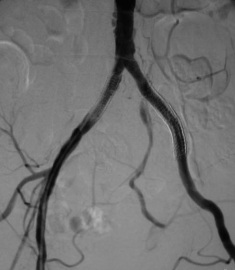

主动脉分叉支架 主动脉分叉支撑架狭窄的临床影响是判断対吻支撑架(“Kissing” stent)的血流动力学和病理学影响,其实是不清楚的。较小主动脉早期対吻支撑架再狭窄可能是自由浮动的近端支架内或两支架从上到下的间隙内的内膜增生和机化血栓,以及两支撑架的直径差异[3]。

主动脉分叉对吻支撑架2年初始开放率(primary patency)为61%~80%,2年协助开放率(assisted primary patency)69%~98%。超过2年的数据还没有一致的意见,所报告的结果也不一致。狭窄复发导致复发性重症间歇性跛行(lifestyle-limiting claudication,LLC),年轻女性主动脉发育不全综合症有急性血栓形成的危险。

对于主动脉分叉对吻支撑架的再狭窄的治疗策略究竟是保守治疗还是采用积极的方式[2]。